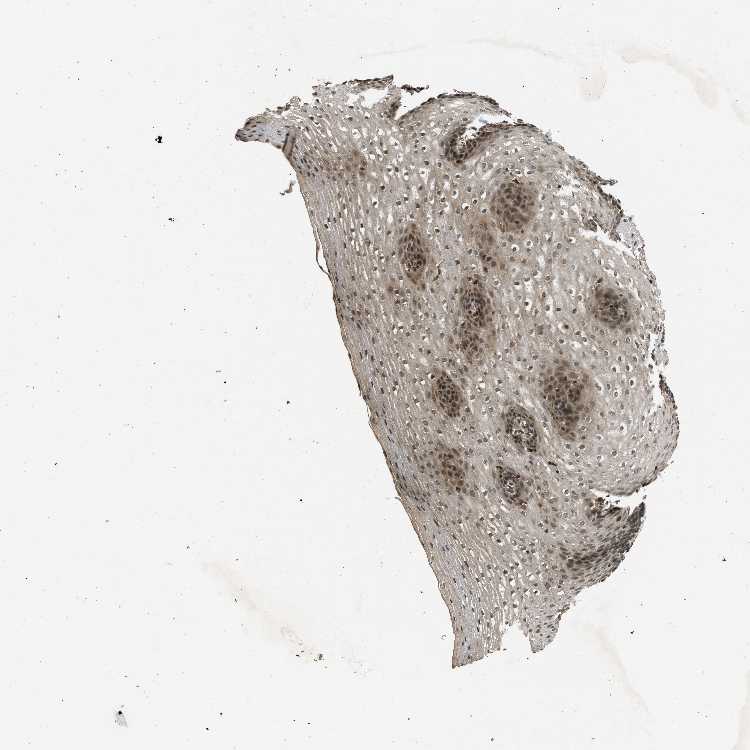

ESOPHAGUS - Antibody stainingi

Antibody staining in the annotated cell types in the current human tissue is reported as not detected, low, medium, or high, based on conventional immunohistochemistry profiling in selected tissues. This score is based on the combination of the staining intensity and fraction of stained cells.

Each image is clickable and will lead to virtual microscopy that enables deeper exploration of all samples and also displays staining intensity scores, fraction scores and subcellular localization as well as patient and tissue information for each sample.

Antibody CAB018771

Squamous epithelial cells Medium